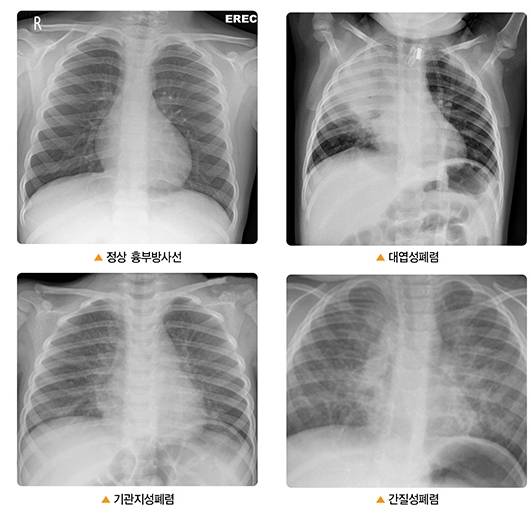

폐렴은 세균·바이러스 등으로 인한 감염으로 폐에 염증을 일으키는 병변이다. 특히 급성폐렴이 발병하면 오한·발열에 이어 호흡 곤란까지 이어지며 상태가 급속도로 나빠질 가능성이 크다. 패혈증·쇼크까지 나타나면서 갑작스레 사망할 수도 있다.

폐렴의 주요 증상은 기침, 가래, 호흡 곤란 등이다. 특히 가래 색깔이 노랗거나 탁하게 변하는 경우가 많다. 발열·오한이 동반되는 경우도 흔하다. 하지만 경미한 폐렴일 땐 특별한 증상이 없거나 피로감·두통·설사 같은 비특이적인 증상이 발생하는 경우도 있다. 정승준 일산백병원 호흡기내과 교수는 "독감과 폐렴은 고열, 오한 등 증상이 비슷하지만, 폐렴이 악화하면 패혈증 쇼크 등이 생기면서 위험한 상황이 벌어질 수 있다"고 경고했다. 독감 환자의 약 10%가 폐렴으로 진행되는데, 고령자와 기저질환자에겐 치명적일 수 있다. 폐렴 치사율은 60대 이후 30%가 넘고, 80대 이상은 50%에 달하는 것으로 알려진다.